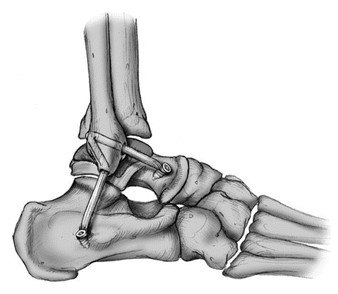

При реконструкции анатомических трансплантатов аутогенные или аллогенные сухожильные трансплантаты помещаются в места прикрепления нативных связок для воссоздания анатомии и механики передней таранно-малоберцовой связки и пяточно-малоберцовой связки. В этих процедурах, трансплантат проходит через туннели в дистальном отделе малоберцовой кости, таранной кости и пяточной кости, чтобы воссоздать как переднюю таранно-малоберцовую так и пяточно-малоберцовую связку (рис.7.2). Трансплантаты сухожилий могут быть фиксированы в кости либо самими швами, либо интерференционными винтами вставленными в костные туннели.

Рис.7.2. Реконструкция передней таранно-малоберцовой и пяточно-малоберцовой связки аутогенными или аллогенными сухожильными трансплантами.

Описана анатомическая реконструкция латеральных связок голеностопного сустава с использованием системы имплантатов Arthrex Lateral Ankle Reconstruction Implant System и Versa Graft [Tourne Y.et al.,2012; Glazebrook M. et al.,2016; Huang B.et al., 2016; Mackay G.M. et al., 2016]. Фиксирующие сухожилие графты проходит через туннели в дистальном отделе малоберцовой кости, таранной кости и пяточной кости и обеспечивает анатомическую реконструкцию передней таранно-малоберцовой и пяточно-малоберцовой связок с простым их натяжением и жесткой фиксацией (рис.7.3 ).